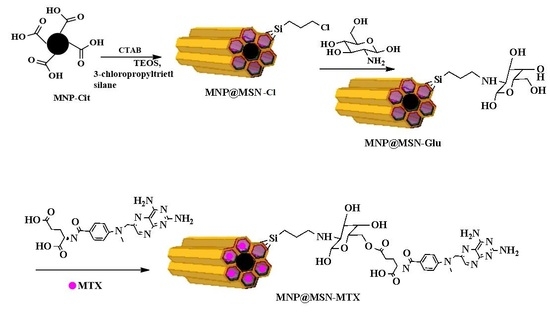

2.3. Synthesis of Glucosamine-Modified Mesoporous Silica-Coated MNP (MNP@MSN-Glu)

2.4. Conjugation of MTX to MNP@MSN-Glu (MNP@MSN-MTX)

3.1. Synthesis and Characterization of MNP@MSN-MTX